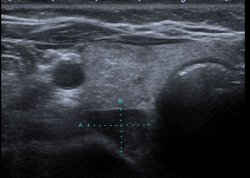

The diagnosis is often discovered incidentally during routine blood work by an elevated calcium level. By detection at an earlier stage of the disease, patients are often without definite symptoms, but severe prolonged primary hyperparathyroidism can lead to kidney stones, osteoporosis and gastric ulcers ("stone, leg and stomach pein"). For localization diagnosis of the altered parathyroid gland, an ultrasound and, if necessary, an additional parathyroid scintigraphy are performed.

Parathyroid adenoma on ultrasound Parathyroid adenoma